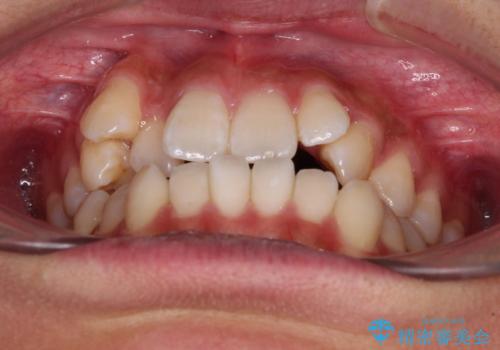

- 前歯の開咬と、上顎前歯の八重歯やデコボコを気にして来院された患者様です。

上顎歯列が狭窄していたため、急速拡大装置により上顎骨を側方に拡大し、その後ワイヤー装置にて矯正治療を行うこととしました。